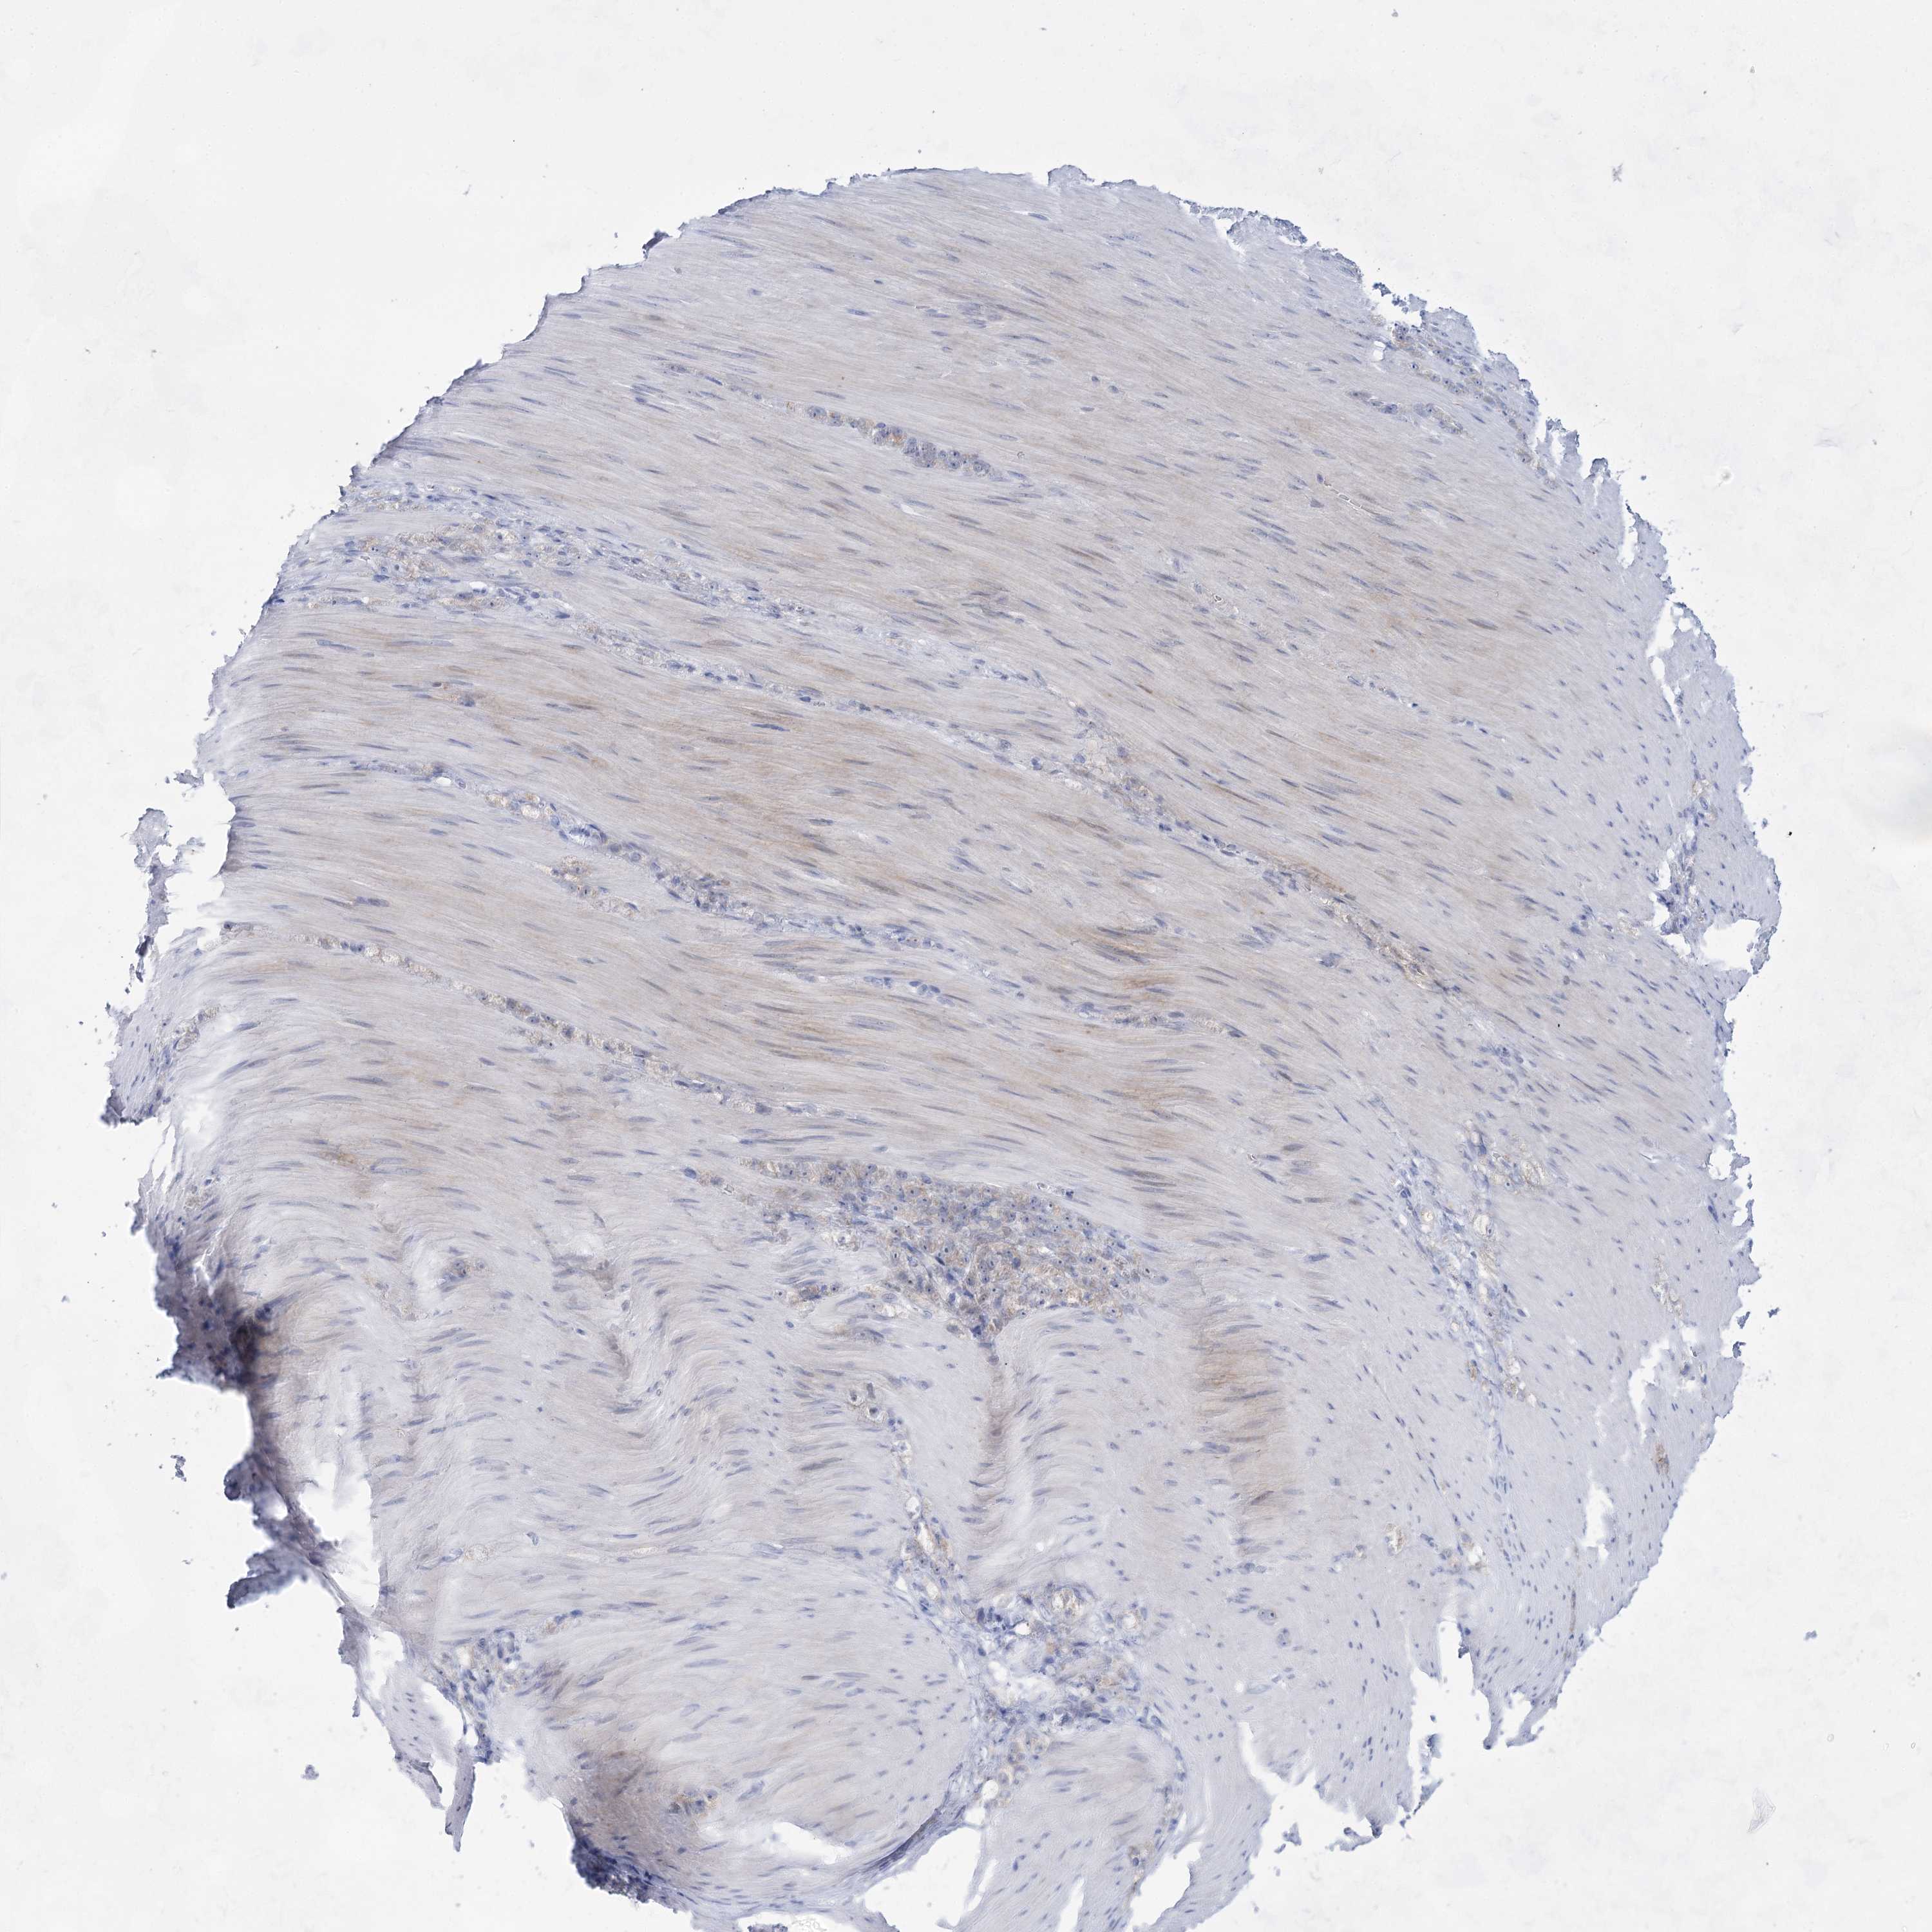

STOMACH CANCER - Protein expressioni

A mouse-over function shows sample information and annotation data. Click on an image to view it in a full screen mode. Samples can be filtered based on level of antibody staining by selecting one or several of the following categories: high, medium, low and not detected. The assay and annotation is described here.

Note that samples used for immunohistochemistry by the Human Protein Atlas do not correspond to samples in the TCGA dataset.

Antibody stainingi

Antibody staining in the annotated cell types in the current human tissue is reported as not detected, low, medium, or high, based on conventional immunohistochemistry profiling in selected tissues. This score is based on the combination of the staining intensity and fraction of stained cells.

Each image is clickable and will lead to virtual microscopy that enables deeper exploration of all samples and also displays staining intensity scores, fraction scores and subcellular localization as well as patient and tissue information for each sample.

Antibody HPA036752

Antibody HPA036753

Adenocarcinoma, NOS